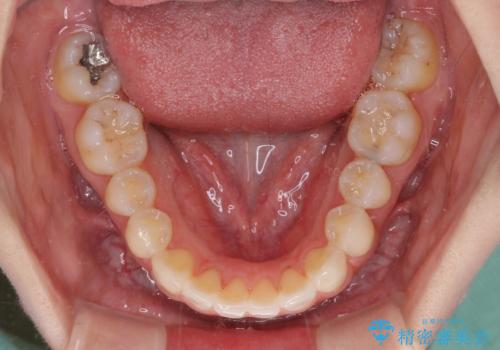

- 前歯のクロスバイトや残存している乳歯を気にして来院された患者様です。

上顎骨の幅が下顎骨よりも小さいので、拡大装置により骨幅を広げて上下関係を改善し、その後インビザラインにて歯並びを整えることとしました。

上下の骨幅を改善したことで、スムーズに歯列矯正を行うことができました。